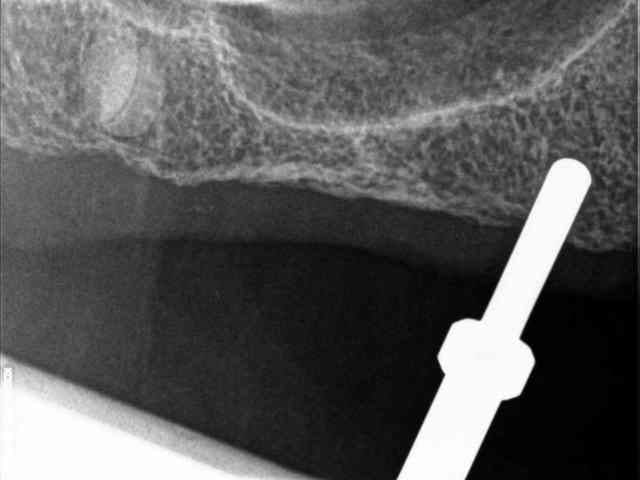

je vous mets les radios per-op.

secteur 1:

à l'aide du guide je détermine la position et l'axe de l'implant.

retrait du guide et contrôle radio puis pose des implants

17/02/2013 à 12h11

secteur 2:

on voit bien ici que cette méthode reste suffisamment précise pour longer le sinus sans le pénétrer.

je n'en demande pas d'avantage.

dentiste57 écrivait:

--------------------

> secteur 2:

> on voit bien ici que cette méthode reste suffisamment précise pour longer le

> sinus sans le pénétrer.

> je n'en demande pas d'avantage.

Cet implant pénètre de 5 à 6 mm dans le sinus.